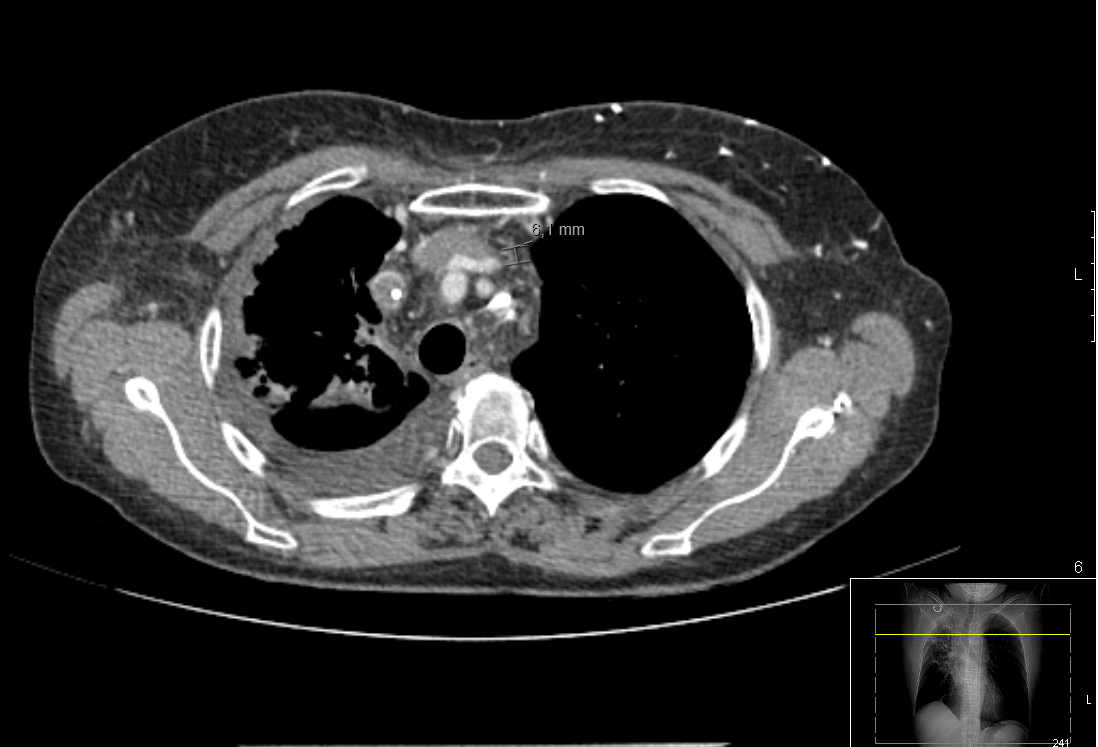

She was admitted to Oncology service, where a scan was done. It revealed a filling defect at left subclavia vein suggestive of thrombosis (Figure 2). Subcutaneous device was withdrawal. We started anticoagulant therapy with subcutaneous Tinzaparin 10,000 UI, every 24 hours. Three months later, a new control scan was done: collateral circulation was still present.

Figure 2 CT scan at Oncology department. It revelaed a filling defect at left sublcavia vein.